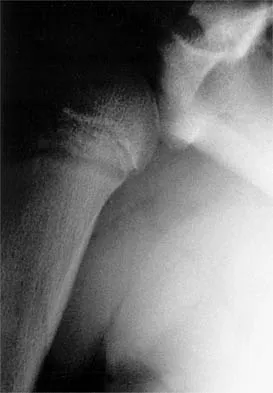

Figure 35 shows the radiograph of a 12-year-old boy who fell off a snowmobile and landed on his left shoulder. He has a closed injury. Management should consist of

Proximal humeral fractures in children are classified as metaphyseal or Salter-Harris type I or II fractures, and most of these fractures are treated with closed methods. Eighty percent of the growth of the humerus comes from the proximal physis; therefore, tremendous remodeling potential is present. Indications for open reduction include open fractures or severely displaced fractures in adolescents with minimal growth remaining. Acceptable limits of reduction in adolescent proximal humeral fractures include bayonet apposition and angulation of less than 35 degrees. Common blocks to reduction in adolescents include the biceps tendon and periosteum. For this fracture, use of a shoulder sling without reduction will lead to healing and an excellent result as the proximal humerus remodels. Kohler R, Trillaud JM: Fracture and fracture separation of the proximal humerus in children: Report of 136 cases. J Pediatr Orthop 1983;3:326-332. Beaty JH: Fractures of the proximal humerus and shaft in children. Instr Course Lect 1992;41:369-372. Dobbs MB, Luhmann SL, Gordon JE, et al: Severely displaced proximal humeral epiphyseal fractures. J Pediatr Orthop 2003;23:208-215. Beringer DC, Weiner DS, Noble JS, et al: Severely displaced proximal humeral epiphyseal fractures: A follow-up study. J Pediatr Orthop 1998;18:31-37.